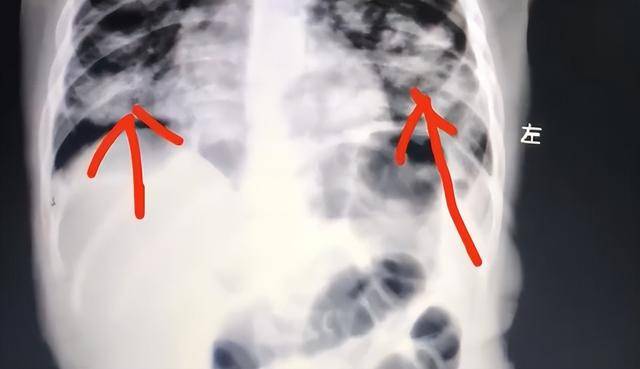

家长发现后,第一反应是立即用手抠孩子喉咙催吐,不料这一做法反而导致油脂被吸入肺部,引发严重吸入性肺炎世界杯皇冠信用平台。目前,孩子肺部已出现大面积感染变白。

据了解,这瓶紫草油原本是家长为孩子涂抹臀部所用世界杯皇冠信用平台。事发时,宝宝不慎误饮一口,母亲情急之下采取催吐措施,却刺激孩子剧烈咳嗽,致使部分油脂被吸入气道,进入肺部。

油脂类物质一旦进入肺部,难以自行排出,会迅速引发炎症和感染,情况十分危险世界杯皇冠信用平台。